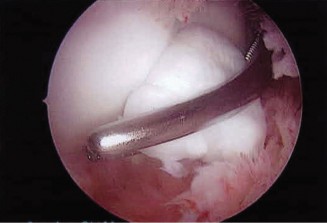

The patient undergoes conservative management consisting of rest, anti-inflammatory medications, and physical therapy. After six months, he is still not able to return to play and has progressively worsening symptoms with attempted throwing. He has a moderate elbow effusion as well as a 20-degree flexion contracture. An elbow MRI arthrogram is obtained and shown (Fig. 2–112). He elects to proceed with elbow arthroscopy. Intraoperative arthroscopic images are shown (Figs. 2–113 and 2–114).

Figure 2–112

Figure 2–113

Figure 2–114